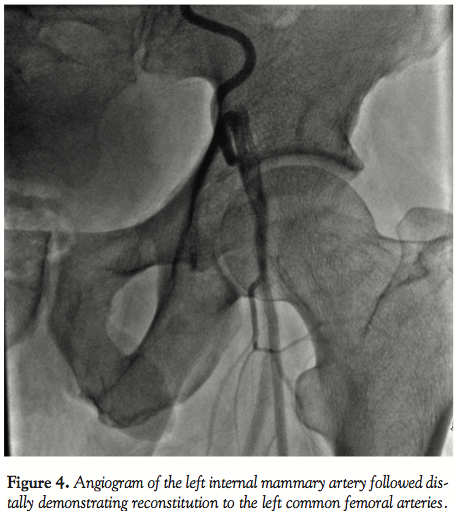

Imaging of the right coronary and circumflex arteries revealed no significant lesion. The left ventricular ejection fraction was normal. The injection into the LIMA showed marked increased diameter (Figure 1) with unusually long collaterals extending to the left common femoral artery (Figure 2). There was a total occlusion of the left common femoral artery (Figure 3) with reconstitution of the common femoral artery from the LIMA collaterals (Figure 4). There was no evidence of coarctation in the proximal ascending aorta identified of the aorta on this or prior coronary angiography studies (Figure 5).

In our case the unusual caliber (5 mm) of the LIMA and its collateralization of the left common femoral artery via the epigastric artery pathway is worth documentation. This condition may be rare, but it is important to realize that such an unusual collateral pathway may be present in cases in which ordinary abdominal aortography and pelvic runoff does not reveal any obvious collaterals compensating an occluded iliac artery.